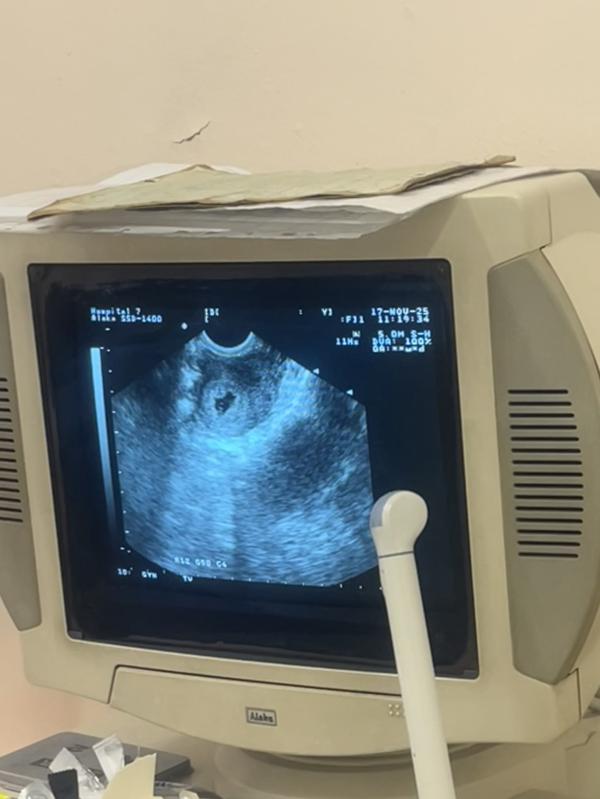

сходила на узи, всё хорошо. растёт моя любовь 🤍🥐

срок 5 недель

сказали рановато, чтобы послушать сердечко, ну или аппарат у них доисторический 😄